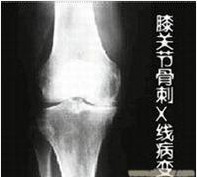

膝关节骨刺是人体自然老化现象,多由于膝关节在长时间反复使用下导致膝关节磨损、破坏,并促成 骨头本身的修补、硬化与增生,多发于中老年人。那么,中老年人膝关节骨刺如何进行保养?下面一起来具体的了解一下。》》》百看不如一问,咨询专家如何对症治疗

中老年人膝关节骨刺如何进行保养?